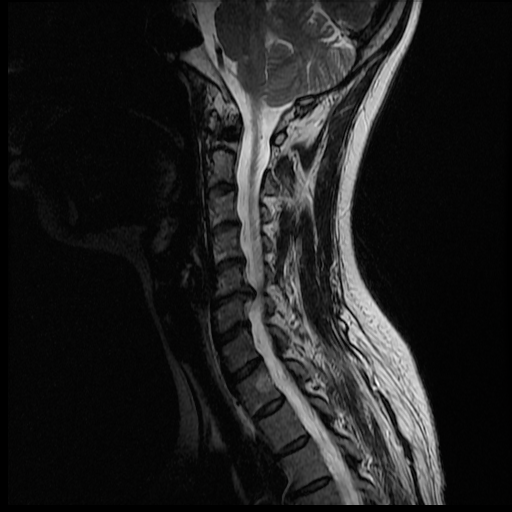

I'm waiting anxiously for Monday morning, but my husband has been pouring over the MRI images most of the night and even this morning. He's not a doctor, but it seems I may have a herniated disc. I hope this is the only thing going on.... The thing is we don't know if this is C6/C7 (where the lesion was seen), or C5/C6. Here are some of the pictures that show that the disc may be bulging/herniated.

Hopefully the experts come to the same conclusion, and that there isn't anything else... only Monday will tell.

Just got a call from my Onco. The report was there and the only thing seen was the degenerative disc! No Evidence of Metastasis!!!!